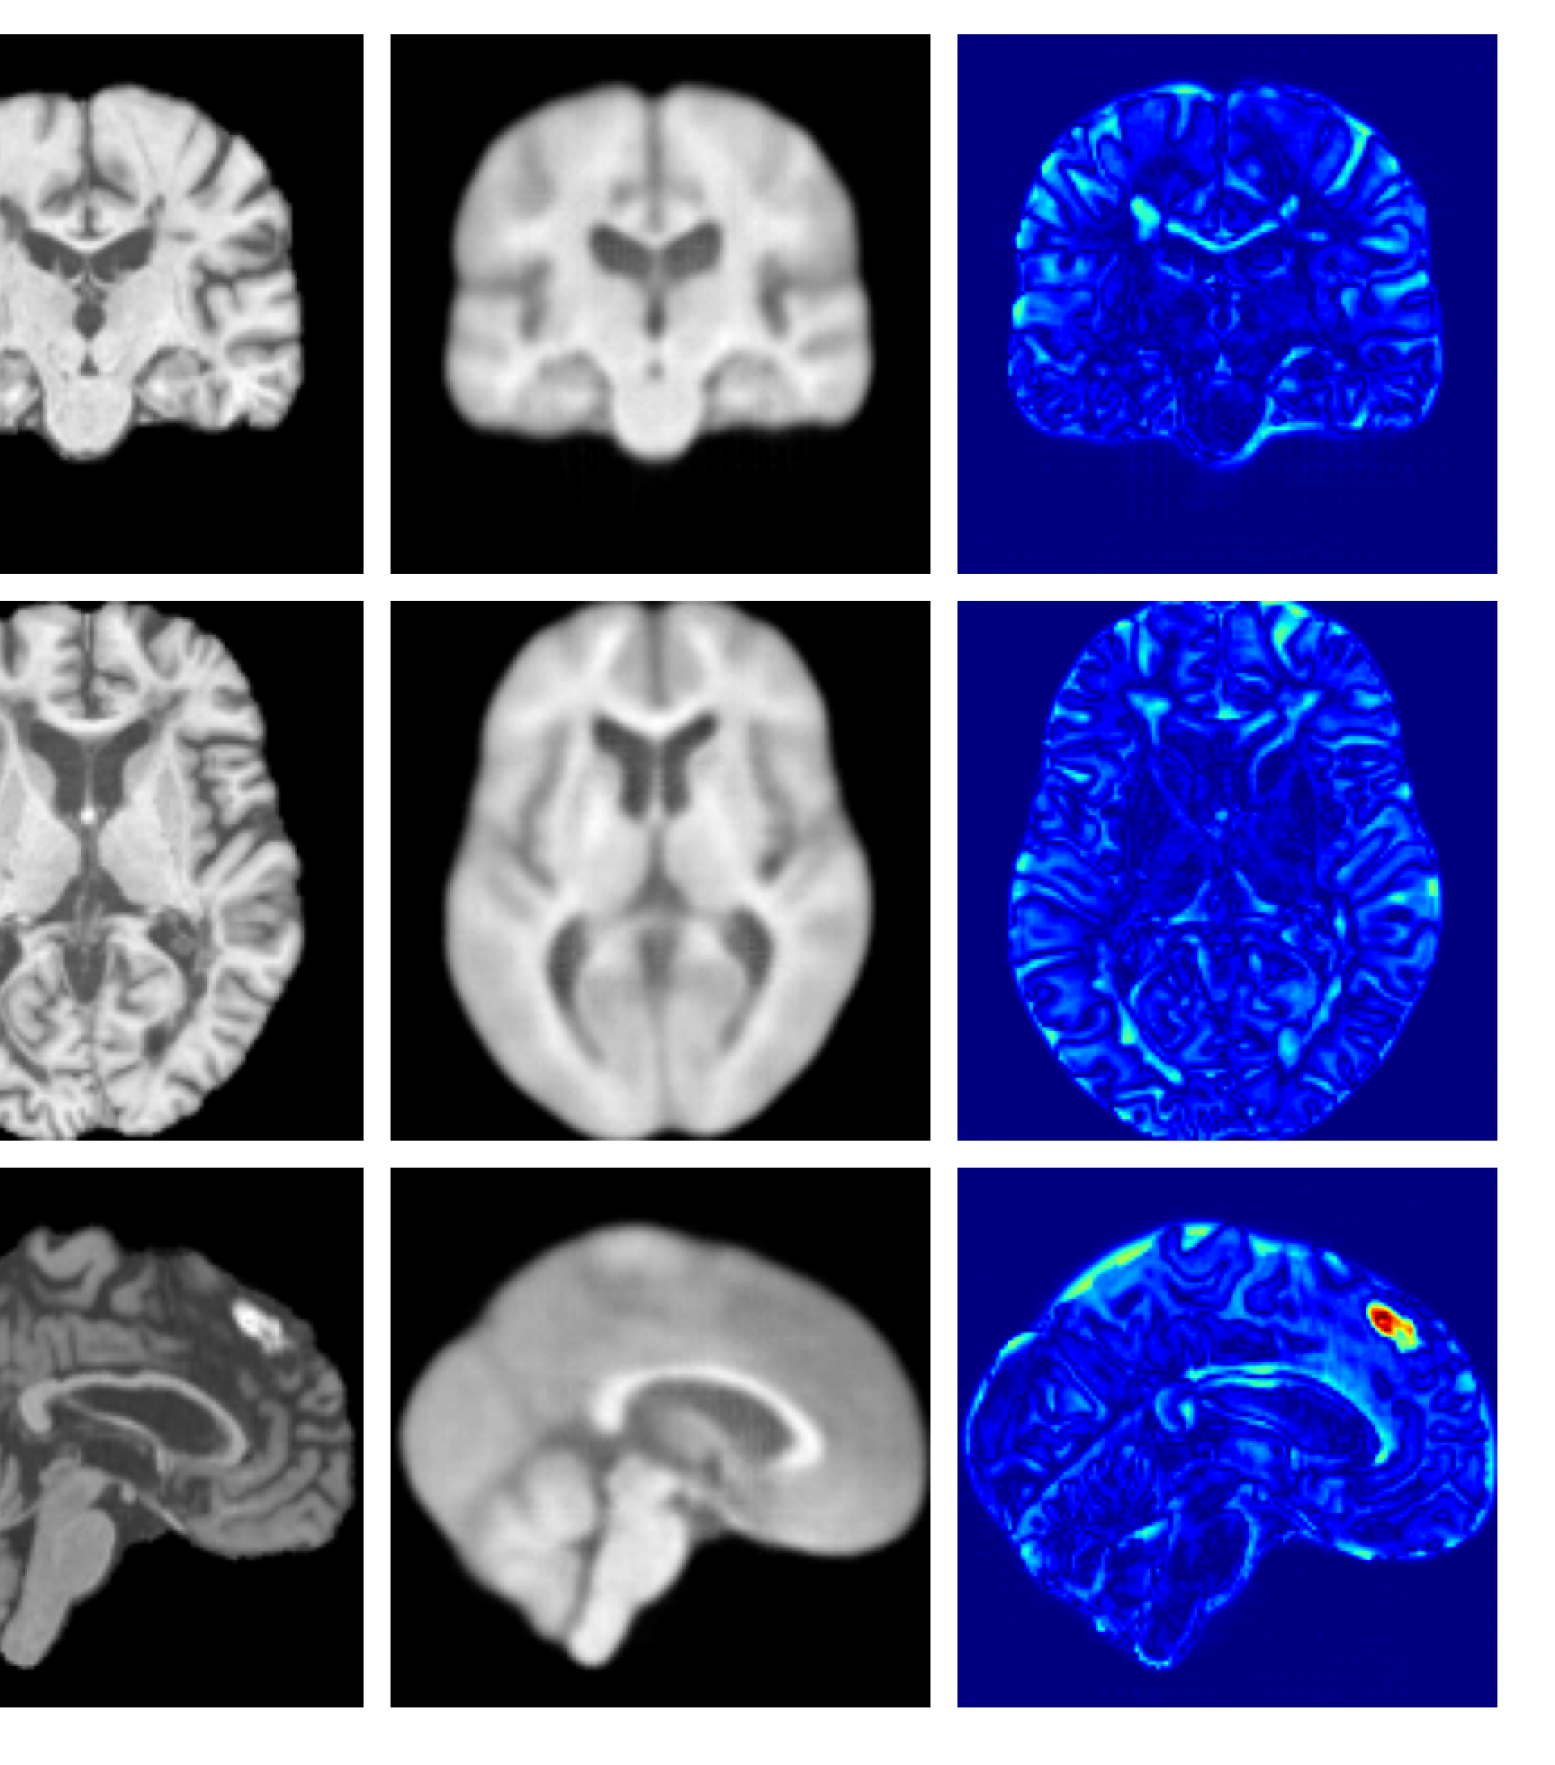

Figures 8 and 9 are enlarged versions of Figures 3 and 4 respectively, with the latter now including results from all compared methods. Figure 10 provides example reconstructions and anomaly maps for an AD subject from the ADNI disease cohort.

Refer to caption

Figure 10: Example reconstructions and anomaly maps for an AD sample from the disease cohort of the ADNI dataset. We expect to see some inpainting of atrophied tissue whilst retaining the defining characteristics of the individual sample.